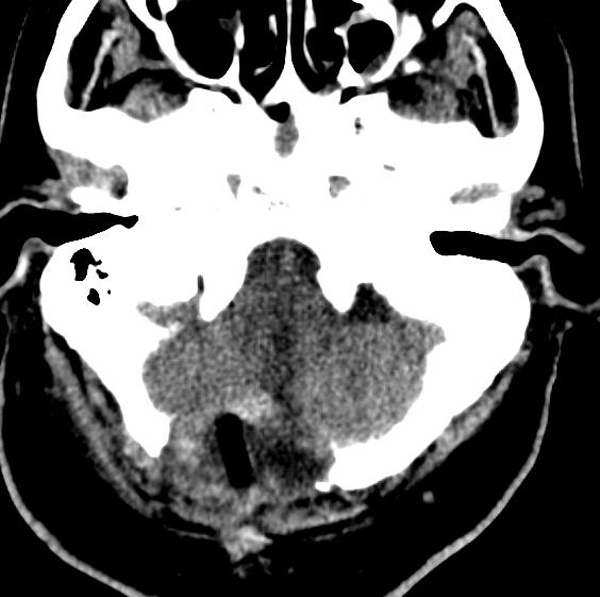

73岁的刘大爷因“言语不利、饮水呛咳及肢体无力”在当地医院以“脑梗塞”住院治疗10天,症状进行性加重,转入二一五医院进一步治疗,神经外科肖三潮教授、谢国强主任通过全院多学科会诊,经过充分评估患者病情后考虑,目前肿瘤占位效应明显,压迫延髓,导致患者呼吸功能紊乱,随时存在呼吸停止可能,唯有尽快手术切除肿瘤才能挽救患者生命,但延髓手术风险极大,术中患者随时存在呼吸心跳骤停可能,向患者家属充分告知手术必要性及危险性,征得家属同意后,12月27日,神经外科肖三潮教授、神经重症监护室谢国强主任、吴东飞主治医师在全麻下为患者行延髓占位切除术。

术中保留患者自主呼吸,严密检测生命体征变化,术中多次出现呼吸及心跳减慢,麻醉师予以兴奋呼吸等积极治疗,最终转危为安,历时6小时,手术顺利完成。术后患者神志清楚,术后三天脱机,右侧肢体功能正常,左侧肢体肌力同术前(3级),目前正在逐步康复中。